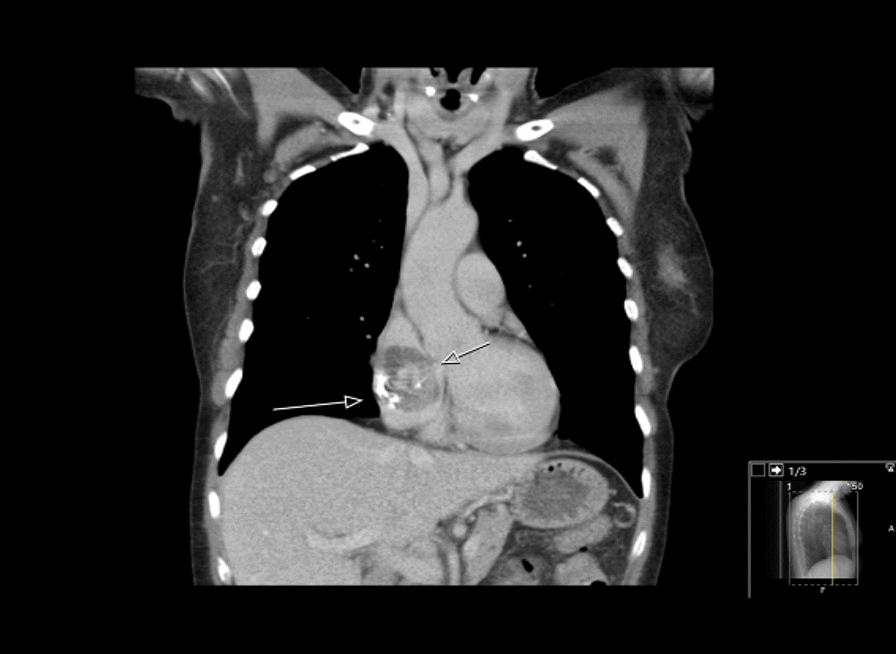

A 58-year-old female with no previously medical history had experienced symptoms for 2 years of recurring sinusitis with periorbital pain, nasal congestion, and fever. Occasionally, blood-strained nasal congestion or nosebleed occurred, and she was diagnosed with chronic maxillary sinusitis. Her symptoms developed to include periodic fatigue, shortness of breath during exercise, nagging cough, ear congestion, and general stiffness without joint pain. Her lab values displayed microcytic anaemia with haemoglobin of 110 g/L (reference 117–153 g/L), mean corpuscular volume (MCV) of 81 femtoliters (reference 82–98 femtoliters) along with signs of inflammation with a C-reactive protein (CRP) of 15 mg/L (reference < 5 mg/L), and erythrocyte sedimentation rate (ESR) of 123 mm/h. Serum creatinine was 52 µmol/L (reference 35–85 µmol/L). The patient with the symptoms and inflammatory parameters was referred from the primary care unit to a diagnostic centre. Furthermore, she underwent a gastroscopy with no source of gastritis or ulcer as a part of an anaemia investigation. The urine protein dipstick test detected no evidence of proteinuria or haematuria. No free light chains and monoclonal immunoglobin were detected in either the blood or urine. Further serological testing was performed, and the outcome was a positive proteinase 3 antineutrophil cytoplasmic antibodies (PR3-ANCA) at the level of 116 IU/mL (reference < 5 IU/mL). The patient was referred to the department of rheumatology. The consideration made was granulomatosis with polyangiitis (GPA) with engagement of the upper respiratory tract with inflammatory activity in lab findings of PR3-ANCA. Induction therapy with 40 mg of Prednisolone per day and 20 mg of Methotrexate once a week was initiated. Prednisolone was then de-escalated biweekly first with 5 mg until a dose of 20 mg was reached. The dose reduction was later lowered by 2.5 mg at the same rate. A nasal mucosal biopsy was performed and revealed pronounced mucosal inflammation. A computer tomography scan revealed a normal appearance of the lungs and a mass of 47 mm in the right atrium (Fig. 1). The patient underwent echocardiography and transoesophageal echocardiogram which revealed a suspicion of cardiac myxoma in the right atrium. A coronary angiogram was performed and showed no evidence of coronary stenosis.

Fig. 1.

CT-scan of the myxoma in the right atrium